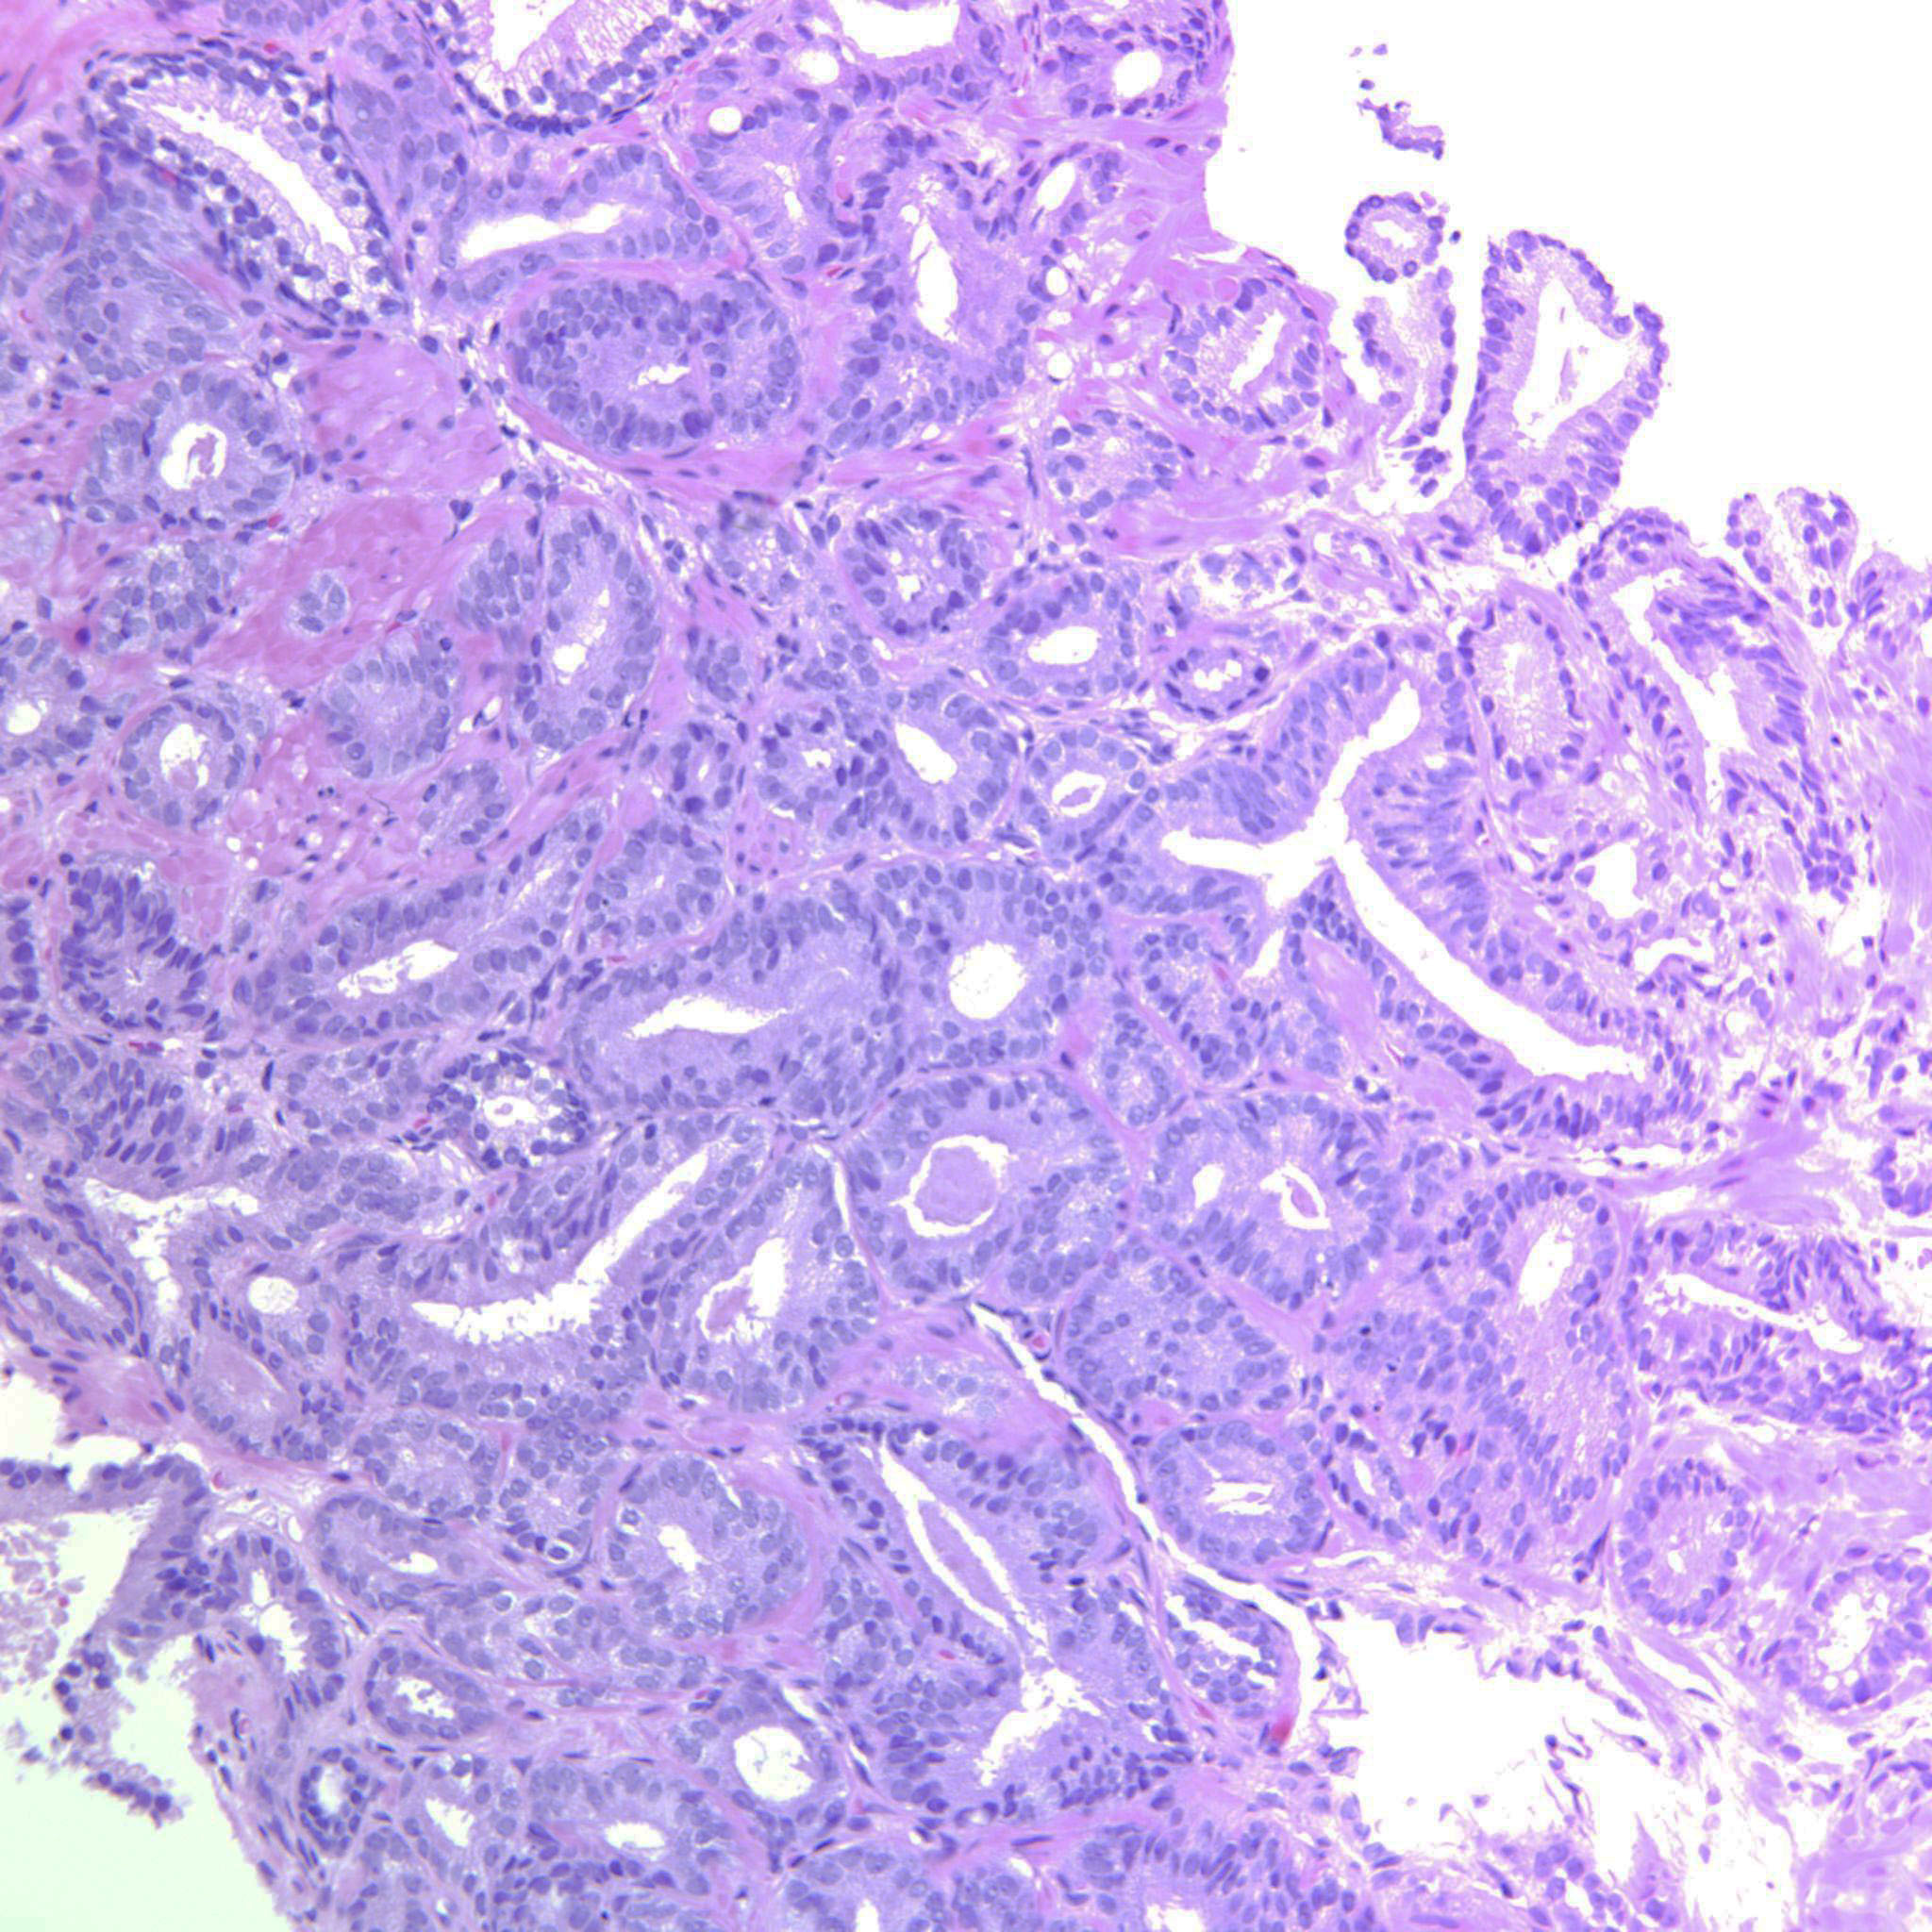

Prostate cancer grading

Case ID: 643